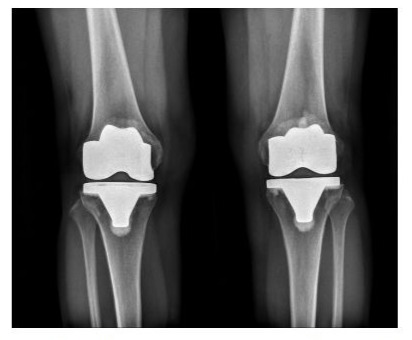

Radiographs of the knees of a 65-year-old woman who had osteoarthritis in both knees (Figure 3).

Figure 3A: Standing anteroposterior radiograph of both knees taken 4 years after surgery, showing that the Freedom knee prostheses are embedded solidly in a satisfactory position. There are no radiolucent lines and there is no osteolysis around the components in either knee.

Figure 3B: Lateral radiographs showing that the Freedom knee prostheses are fixed satisfactorily. There are no radiolucent lines and there is no osteolysis around the components in either knee.

The radiographic results were similar in the NexGen LS-Flex and Freedom TKA groups with regard to the alignment of the knee and the position of the femoral and tibial components in the coronal and sagittal planes. If one assumes a tolerance level of 3°, then the prevalence of outliers ranged from 2 to 4% for all parameters in the NexGen LPS-Flex TKA group and from 1 to 3% in the Freedom TKA group. These differences between the groups were not significant (P > 0.05; Table 4). No knee in either group had osteolysis around the components (Figures 2 and 3).